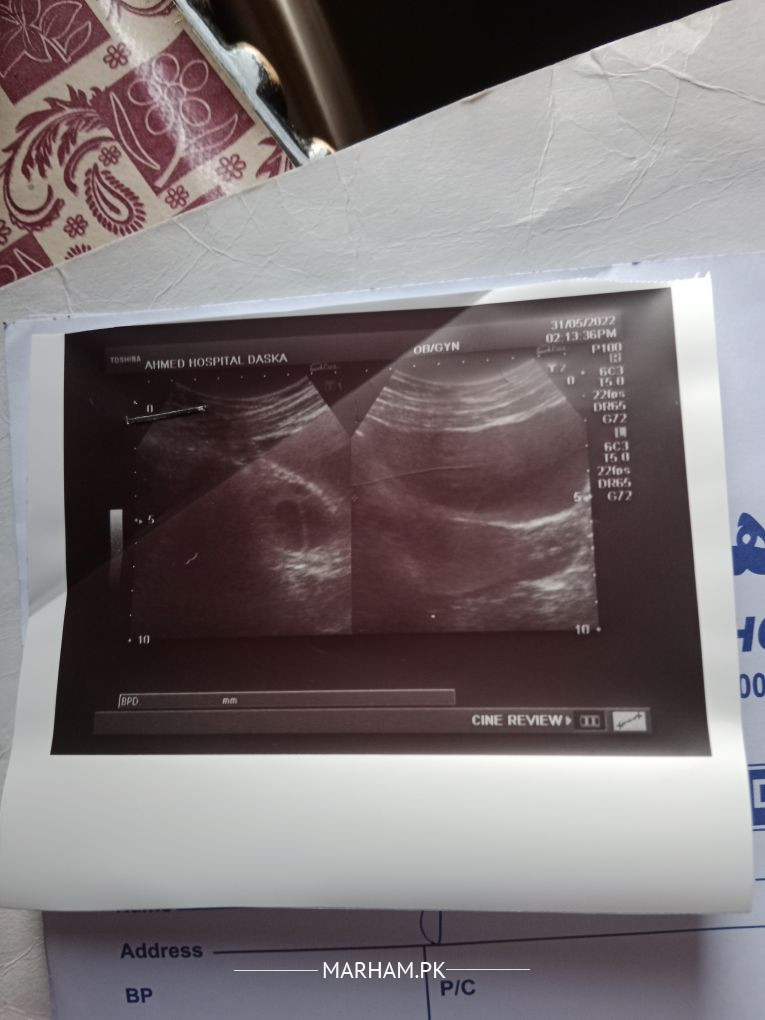

ma conceive k treatment Le rhi hun 4montj hai .11 day pe scan krwA egg size kindly check .and 2 ivf c injection lgwy hai day 12 pe. can I conceive kindly bta dn.

Attach Photo here: